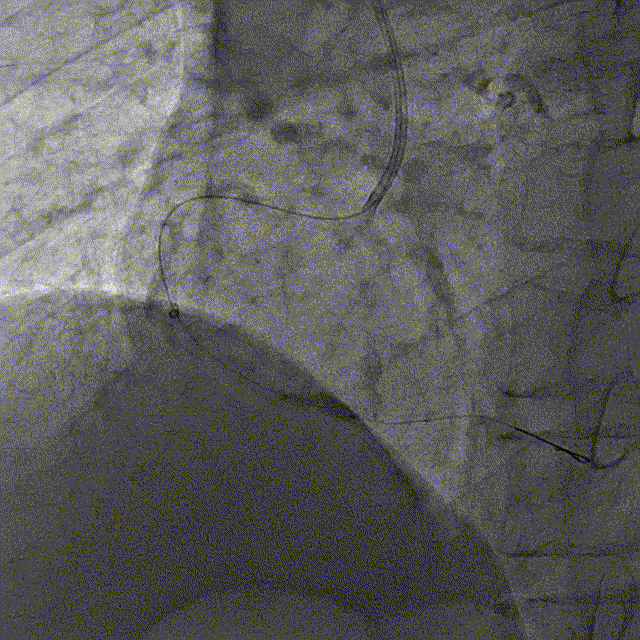

冠脉造影结果:LM外膜钙化,内膜不光滑,中段狭窄90%,TIMI3级。LCX外膜钙化,内膜不光滑,TIMI3级。RCA外膜钙化,内膜不光滑,近段狭窄80%,中段狭窄90%,可见破损斑块,TIMI3级。

冠脉内介入治疗